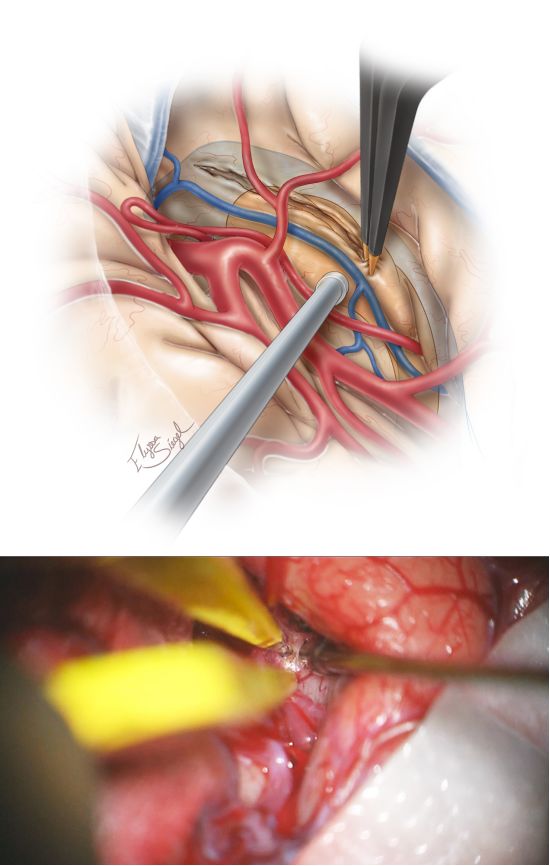

图5. 下一步识别M1及M2近端分支,同时分离显露出岛下部及颞干。笔者在岛下沟的皮层做最初切口(10-20mm),起始部后方或周围见颞极动脉、旁外侧裂下静脉,电凝处理之。此切口也需要术中导航,可标注颞角及海马的大致位置(上图)。

图6. 切开颞干后进入颞角,形成了可探及海马及杏仁核的视野通道。由于之前脑脊液释放后使脑室塌陷,颞角不一定能立即清晰显露。斜面的脑白质容易使术者困惑,因此常规应用神经导航引导下分离此处及切除杏仁核外侧以暴露前颞角。

图7. 应用超声刀、双极电凝及吸引器仔细完整切除杏仁核。该法可在残留蛛网膜中可见海马(中图)、小脑幕内缘(蓝色箭头)及动眼神经(黄色箭头)(下图)。自MCA分叉处至脉络丛前缘的虚线划出了杏仁核的上缘。

图8. 安全分离海马前部(海马头),自后向前切除。第二步切除海马体、尾部,自前向后一条深在的手术路径可抵到海马后部。

图9. 切除海马的手术技术与上述切除杏仁核相似。手术在脉络丛外、基底池蛛网膜上方的软脑膜下进行,这些膜层需得到保护,而海马旁回在软脑膜下切除。脉络膜前动脉未暴露,大脑后动脉(PCA)(红箭头)得到了保护,给海马后半部供血的侧副沟内穿支(黑箭头)被分离出来以双极电凝切除,以避免脑组织及血管的撕脱。

图10. 在脉络丛外侧及基底池蛛网膜层的薄层脑组织被保留下来,避免损伤脑干及间脑组织(上图),术中应注意最小化侵扰术区相关解剖。

SA的手术操作通路虽狭长,但应尽可能避免牵拉或操作引起的MCA分支损伤。显微操作脑压板可动态牵拉;开始外侧裂广泛分离时应避免对额颞叶组织的损伤性牵拉;小脑幕内缘是保护基底池邻近组织的可靠标识;小脑幕边缘蛛网膜层若受到过大牵张力时,可导致滑车神经功能障碍而致短暂术后复视。